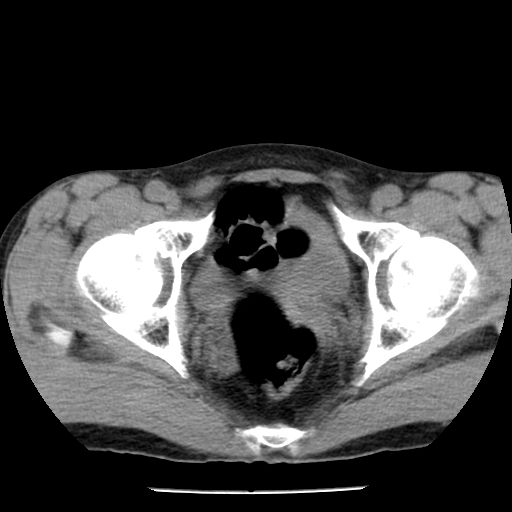

男,59岁,“结核性胸膜炎”30余年,胸部经常疼痛,多次x检查提示“肺部”炎症。腹部疼痛5日,b超提示:“肝内短管结石,余显示不清,建议进一步检查。”

两肺结核并右侧胸腔积液;脾脏、腹腔及腹膜后淋巴结结核[陈旧性];肝内胆管结石。直肠息肉?